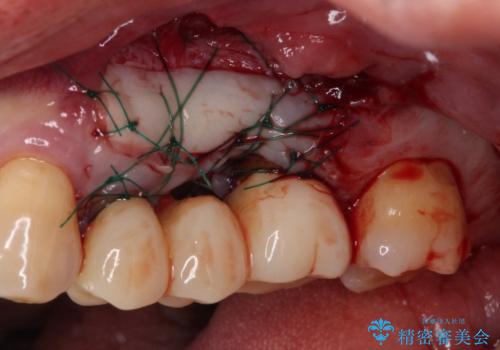

3歯のクラウンを除去し、破折が疑われる歯をチェックしたところ、予想通り破折していたため、抜去することとしました。

抜歯後、骨吸収量が多く、歯肉のラインが不揃いとなっているため骨造成術を、硬い歯肉が失われて清掃性が低下するため角化歯肉の移植術を行い、また並行して支台歯の根管治療を行っていき、環境を整えた上でオールセラミックブリッジにて補綴治療を行うこととしました。

インプラントによる補綴治療も検討しましたが、骨吸収量が多いこと、後方の支台歯が今後抜歯となる可能性が否定できないことを鑑み、将来抜歯となった際にインプラント2本を埋入することで患者様と事前にお話をしました。